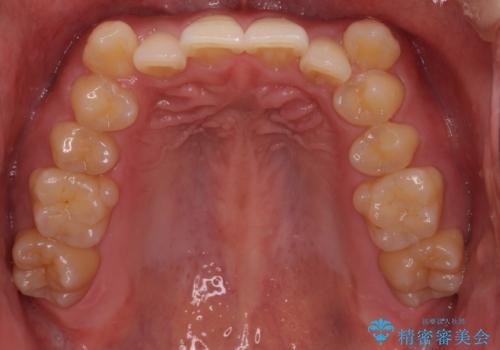

- 上顎の八重歯と前歯のデコボコを気にして来院された患者様です。

八重歯の移動量が多く、インビザライン単体での治療は困難と判断し、補助装置により八重歯移動後にインビザラインを用いることとしました。

上顎のみの抜歯矯正をインビザラインで行う場合、奥歯の前方移動がインビザラインでは苦手のため、奥歯の咬み合わせが不十分となることがあります。

今回の治療では終了時に奥歯は接触しているものの、接触の程度は物足りないものがある状態でした。今後保定期間に少しずつ奥歯の咬合を改善させていくことになります。